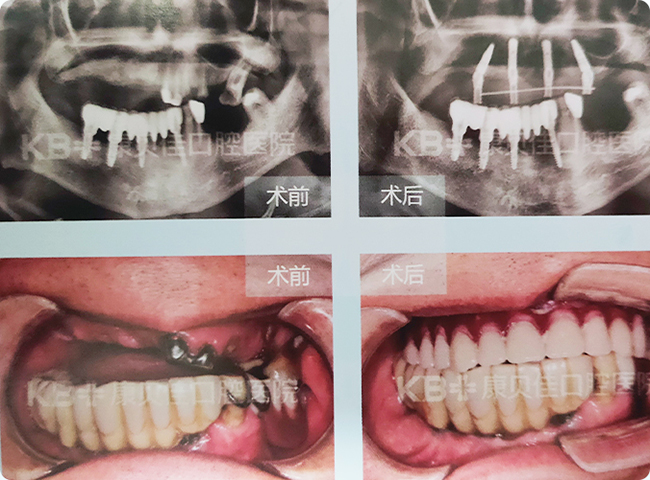

赵先生 74岁

由于缺牙时间长牙槽骨萎缩厉害,活动假牙也越来越戴不住了。在朋友的介绍下到康贝佳,采用种植4颗植体技术恢复了上半口牙,下半口采用“缺多种少”方案恢复。

治疗方案:

上颌种植4颗修复半口 下颌种植4颗恢复8颗